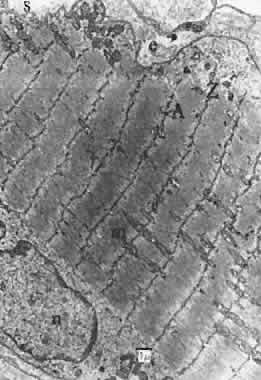

Almost all investigators find that the extraocular muscles of mammals are divided into two layers to some extent: a global or central layer, next to the eye, and a superficial or orbital layer confined to the posterior two thirds of the rectus muscles and less evident in oblique muscles. This layering is much less obvious in humans than lower species (Fig. 17). The orbital layer has a high capillary density and generally contains small fibers. Scott and Collins confirmed that, in humans, fibers that are active constantly for fixation near the primary position are predominantly in this layer.26 By the classification of Alvarado and Van Horn in cat, the orbital layer contains two fiber types.27 Both are relatively small, rich in mitochondria, and contain some lipid vacuoles. About 60% to 70% of the cells are singly innervated with good sarcoplasmic reticulum content, which allows rapid calcium ion changes with each contraction, and about 30% to 40% are multiply innervated slower fibers.

Fig. 17. Section through the middle of rabbit superior rectus muscle. The orbital layer (top) of smaller fibers is obvious.